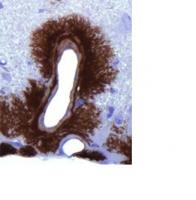

SYNUCLÉINOPATHIES : Un test sanguin pour les distinguer

Actualité publiée le 15/11/2019PARKINSON : La parvalbumine, la protéine qui prévient les fibres amyloïdes